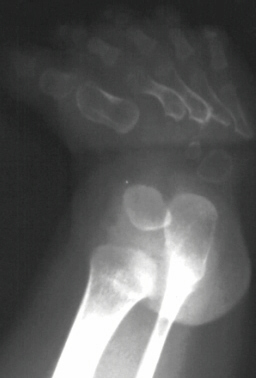

This is a two year old girl who was the product of a normal

gestation. She has two healthy half-sisters. At birth the following

problems were noted: 1. Disproportionate short-limb dwarfism with

hitch-hiker thumbs, 2. Cleft palate, 3. Bilateral clubfoot (left

worse right), 4. Respiratory difficulties because of laryngomalacia,

5. Lack of extension in elbows and knees (moderate) and 6. Cauliflower

deformity of ears occurred in the first weeks of life. She started

walking at the age of 17 months (with some flexion of hips and

knees).